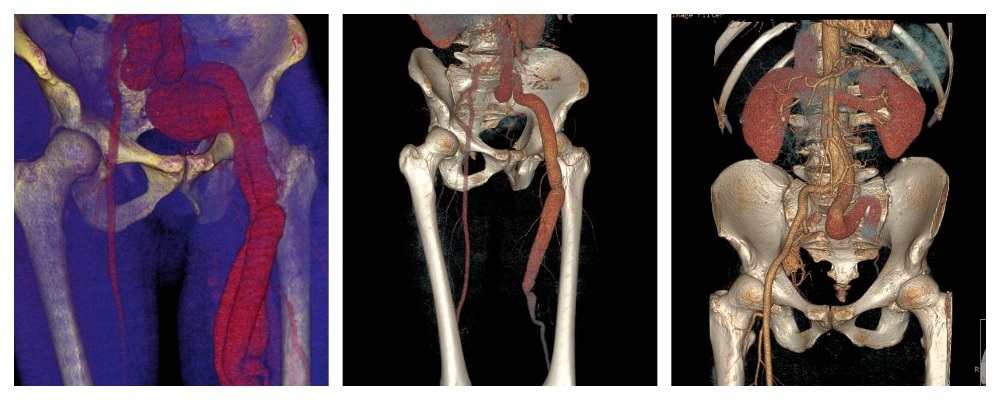

По результатам ЭХОКГ выявлена значимая перегрузка правых отделов сердца. Во время КТ ангиографии врачи обнаружили артерио-венозное соустье в области подколенной ямки (патологическое сообщение между артерией и веной, приводящее к перегрузке сердца). За годы функционирования этой артерио-венозной фистулы произошло расширение артерио-венозной стенки, что привело к значительному расширению артерии. Это грозило разрывом аорты или развитием аневризмы сердца.

Специалисты центра сердечно-сосудистой хирургии госпиталя Вишневского выполнили протезирование подколенной артерии с перевязкой артерио-венозного соустья, после которого при контрольной КТ ангиографии уже через год были отмечены улучшение и стабилизация сердечных показателей. У пациента пропала одышка, увеличилась дистанция ходьбы, и он смог вернуться к нормальному образу жизни.